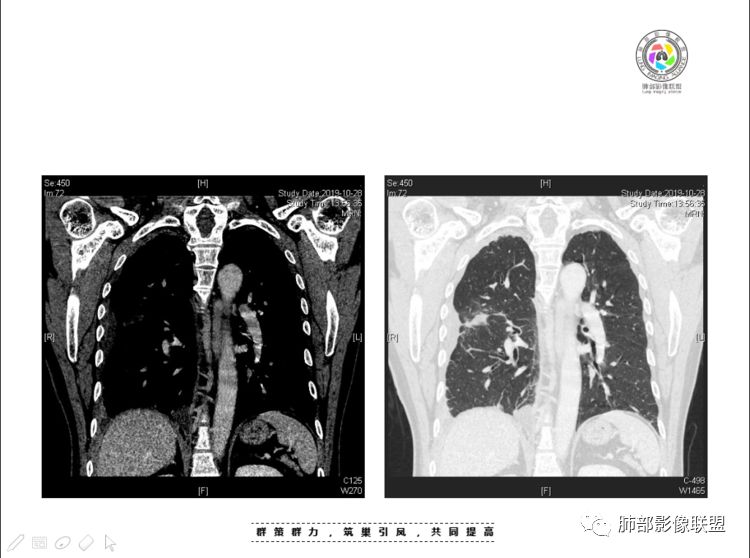

本例纵隔与肺内两处病变,回顾总结分析:

1、右肺内病灶,病灶呈结节样,边缘欠规则,局部膨隆,叶间裂胸膜牵拉凹陷,再看相应支气管腔堵塞截断,临床资料胸水中查到癌细胞,均提示病灶倾向恶性,腺癌的病理意见与之相吻合。

黄勇老师总结,腺癌如果与胸膜、叶间裂紧贴或伴胸膜凹陷,胸膜、叶间裂多发结节,应当高度怀疑腺癌转移。

2、前纵隔内病灶囊实性混杂密度病灶,囊性病灶主要位于右侧,张力较高,有分隔影,囊壁右侧缘光整,病灶左侧实性部分边界不清明显强化,病灶肺瘤交界面大部分边界清楚,部分模糊。